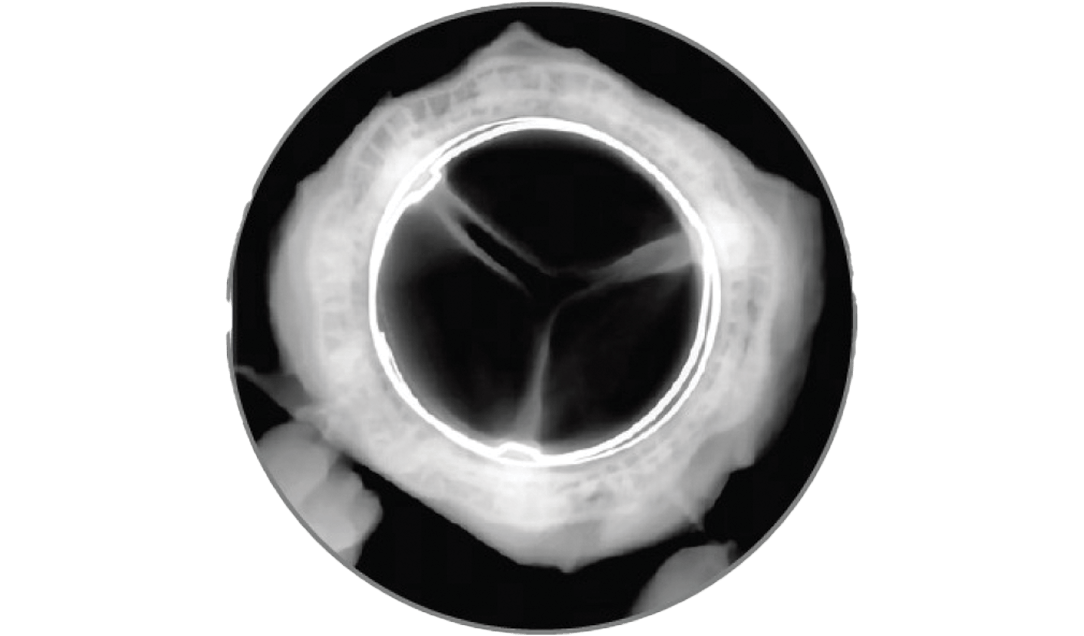

Clinically stable hemodynamics and one incident of structural valve deterioration (SVD) through 5 years.

Reduced calcification after 8 months, exceeding the 5-month reporting requirement